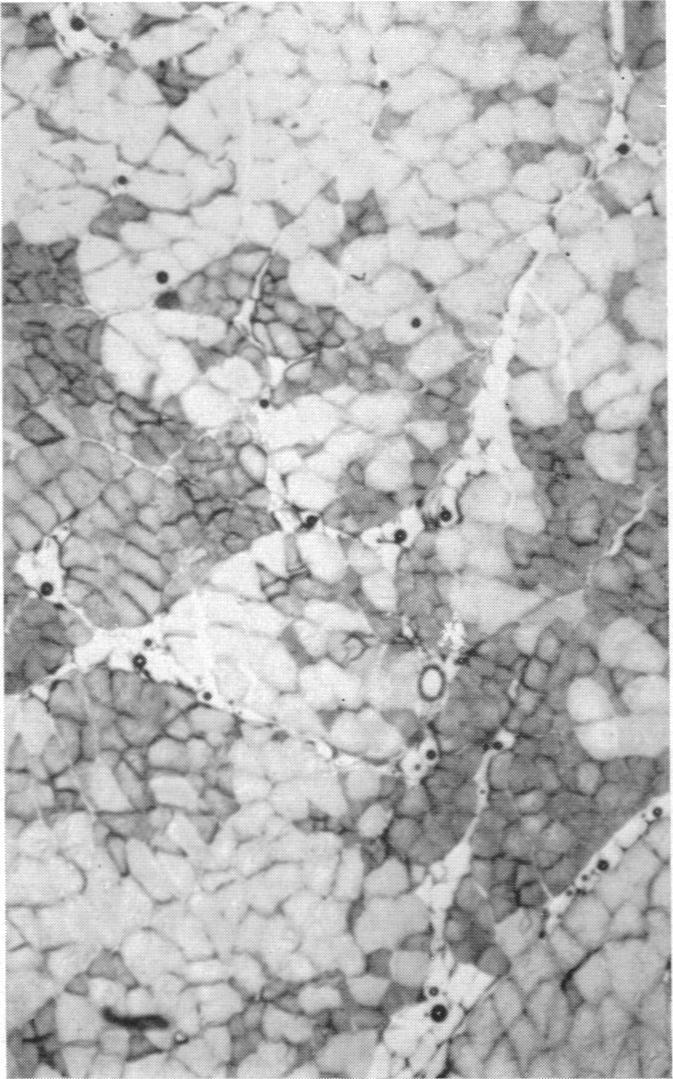

1. Cross-innervation of the slow soleus and fast flexor hallucis longus or flexor digitorum longus muscles has been performed in new-born kittens and rabbits and in adult cats.2. The effects on the histochemical and structural properties of the muscle have been studied and compared with the changes in the contractile properties.3. Cross-innervation has produced a dramatic change in histochemical pattern in the fast muscles, with the development of areas of muscle fibres indistinguishable from normal soleus muscle. The converse change from the histochemical pattern of slow soleus to that of fast muscle has also occurred, but has been less consistent.4. It is concluded that the neural influence determining the contractile properties of fast and slow muscle also has a profound controlling influence on the structure and metabolic activity of the muscle fibres.5. No significant changes could be demonstrated biochemically in the ATPase activities of the fast and slow muscles following cross-innervation.

3. 交叉神经支配使快肌的组织化学模式发生了显著变化,出现了与正常比目鱼肌难以区分的肌纤维区域。从慢比目鱼肌的组织化学模式向快肌模式的相反变化也有发生,但不太一致。